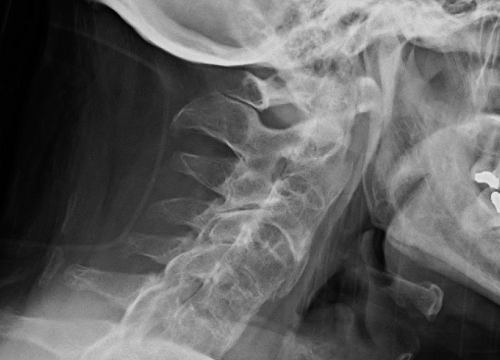

עמוד שדרה – שינויים רדיוגרפיים בעמוד השדרה באים לידי ביטוי עם התקדמות המחלה ונראים היטב בצילומים לטרליים. שינויים אלו כוללים "התרבעות" של החוליות עקב דלקת של המשטח הקדמי והאחורי ויצירת עצם בתגובה לדלקת. בשלבים מתקדמים יותר ניתן לראות סינדזמופיטים ואנקילוזיס של מפרקי הפצט וכן סינדזמופיטים קדמים היורדים מחוליה עליונה ועולים מחוליה תחתונה עד היווצרות גשר גרמי הנקרא – bridging syndesmophytes. בשלב המתקדם ביותר מתקבלת התמונה האופיינית של עמוד שדרה של במבוק. להבדיל מדלקת חוליות מקשחת, היווצרות סינדזמופיטים נדירה ב- nr-axSpA. בבדיקות הדימות השונות ניתן להתרשם גם ממעורבות דלקתית של מפרקי הירכיים ושל מפרקים פריפריים נוספים. אנתזיטיס נראית היטב בבדיקת US ב- B-mode עם power Doppler או בבדיקת MRI.